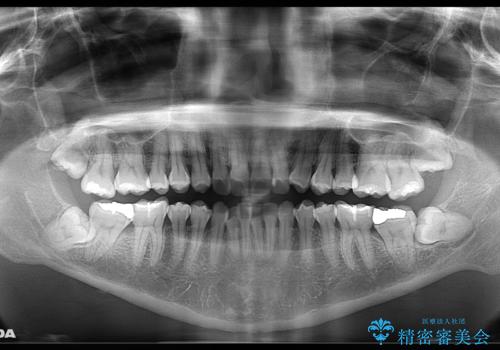

- 前歯を後ろへ下げることを主訴に来院された患者様です。

10代の時に非抜歯でワイヤー矯正をしていました。

口元の突出感の改善や歯の移動量などを考慮し、抜歯を伴うワイヤー矯正での治療を選択しました。

抜歯を行うことで前歯を後ろへ下げるスペースを獲得し、口元の突出感や歯のガタつきを改善していきました。